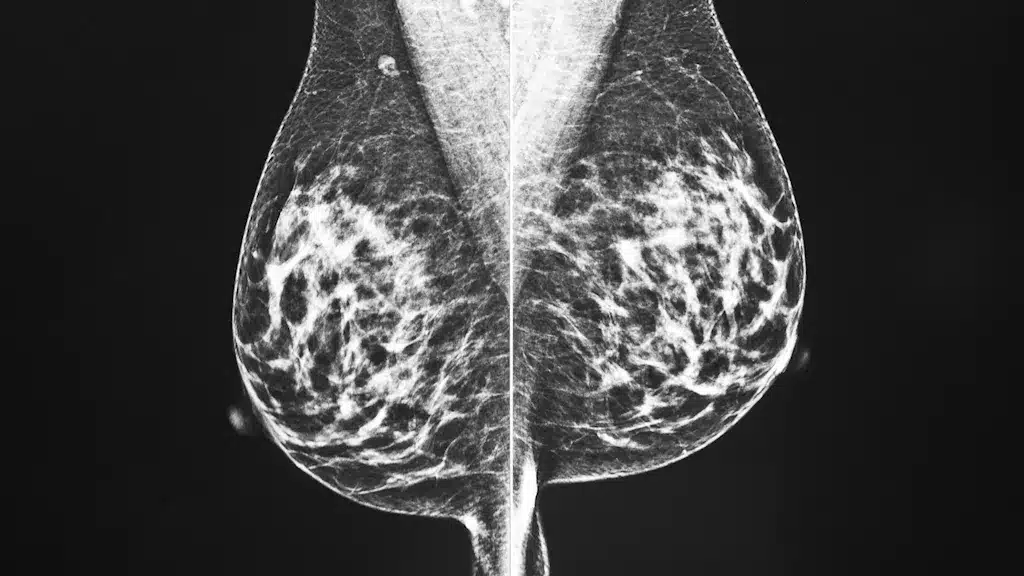

- У половины женщин в возрасте от 40 до 74 лет плотная ткань молочной железы, что затрудняет выявление рака молочной железы.

- Согласно новому исследованию, обследования с использованием МРТ и ультразвука дают лучшие результаты, чем только рентген.